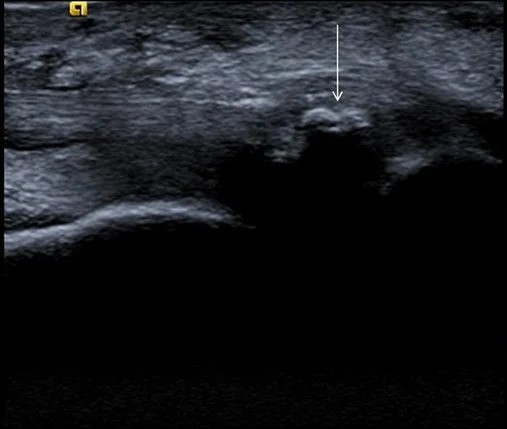

Imagen ecográfica de una calcificación en el tendón tibial posterior

En este eje largo, la calcificación se presenta como un hallazgo focal muy llamativo. Se observa una mancha intensamente blanca (hiperecoica) señalada por la flecha, que rompe la arquitectura habitual del tendón.

El signo diagnóstico definitivo es la sombra acústica posterior: esa zona negra que se proyecta justo debajo del depósito de calcio.

Esto ocurre porque el mineral es tan denso que impide el paso de los ultrasonidos, creando ese «vacío» de imagen característico que permite diferenciar una calcificación de cualquier otra lesión del tejido.